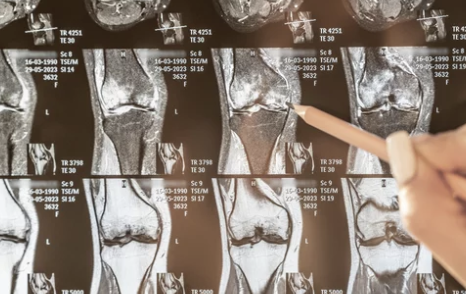

3. 무릎 관절삼출 진단 방법

✅ 병원에서 진행하는 주요 진단 검사

검사 방법 설명

| X-ray 검사 | 무릎 관절의 골절, 뼈의 이상 여부 확인 |

| MRI 검사 | 연골 손상, 인대 파열, 관절 내 염증 확인 |

| 초음파 검사 | 무릎 내부의 염증 및 관절액 증가 여부 평가 |

| 혈액 검사 | 류마티스 관절염, 통풍 등의 염증 수치 확인 |

| 관절액 검사 (관절천자) | 주사기로 관절액을 채취하여 감염 여부, 염증 원인 분석 |

📌 TIP:

- 무릎 관절염과 연골 손상 여부를 구별하기 위해 MRI 검사가 효과적입니다.

- 류마티스 관절염이나 감염성 관절염이 의심될 경우, 혈액 검사 및 관절액 검사가 필수적입니다.